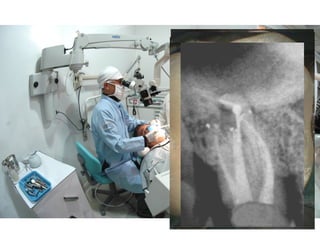

• #13 Este paciente apareceu no consultório com muita dor. A radiografia revelou área de radioluscência – uma área radiolúcida na região periapical – diagnóstico de abscesso agudo secundário: DISCUTIR – abscesso agudo primário e secundário – apenas para recordar. Abscesso secundário é de longa duração. Abscesso primário é de curta duração. Na teoria fala-se que o secundário é mais difícil quanto à cura. Na prática isto não importa. O tratamento é o mesmo o a biologia molecular da reparação é absolutamente a mesma. Eu acredito muito na EXPERIÊNCIA PROFISSIONAL...Esta não deve ser confundida com PRINCÍPIO DE AUTORIDADE. Experiência Profissional e Princípio de Autoridade são duas coisas diferentes. Por favor, peço para não confundir... Abscesso é uma coleção e pus. Pus é formado por água – exsudato inflamatório de origem do plasma sanguíneo – origem plasmática – com células mortas e restos teciduais – restos de tecido. Este corte histológico do Prof. Alberto Consolaro (130) uma coleção de pus – ver RX – no centro do abscesso, circundado, envolvido por uma grande concentração de neutrófilos – infiltação neutrofílica dentro do círculo. Na periferia temos o tecido de granulação rico em vasos e células jovens – neutrófilos que substituem àqueles perdido, destruidos, macrófagos, plasmócitos e fibroblastos jovens com grande potencial – poder de síntese – com a finalidade de cura – reparação da lesão após a eliminação da injúria microbiana. As figuras BCDE são neutrófilos. Observações: Núcleo com várias formas – polimorfonucleares – o citoplasma é claro nos cortes corados em HE. A figura E mostra numerosos lisossomos no citoplasma. Lisossomos são organelas carregadas de enzima proteolíticas – destruidoras do osso alveolar. No corte histológico do Prof. Alberto Consolaro (164) vemos uma concentração de bactérias organizadas em biofilmes. A extrusão de produtos tóxicos – toxinas (exotoxinas) enzimas e produtos do metabolismo celular – induzem a inflamação – setas – Na região do terço apical do canal as bactérias sobrevivem por dois fatores: 1. São alimentadas pelo tecido necrosado – banquete para os microorganismos e 2. Não sofrem ataque do sistema inflamatório – imunológico por conta da ausência de circulação que impede a chegada de leucócitos e mediadores químicos que as eliminariam. No corte vemos Biofilme microbiano. Pelo forame saem produtos tóxicos e lesivos aos tecidos periapaicais – cemento, ligamento periodontal e osso alveolar e eventuais bactérias. Neutrófilos fixam-se na região periapical, no canal cementário. A linha pontilhada marca a região ocupada pela inflamação crônica caracterizada pelo granuloma periapical com macrófagos, linfócitos, plasmócitos e o tecido de granulação (fibroblastos e vasos sanguíneos neoformados). Envolvendo tudo o corte revela uma cápsula fibrosa – cápsula de tecido conjuntivo fibroso de proteção. Fiz o tratamento endodôntico – descrever – discutir – Trefinação – Reparação – Resposta inflamatória crônca (222) comentar: Macrófagos, Linfócitos e Plasmócitos TREFINAÇÃO : DRENAGEM VIA MUCOSA: 1. Penetração com instrumento fino esterilizado 2. Penetração com curetas finas 3. Desorganização do tecido necrótico purulento 4. Remoção mecânica (como se fosse espremer uma espinha). Pela fístula artificial sai tecido de granulação, sangue e pus.